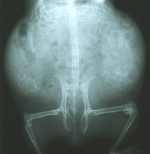

| Für alle medizinisch Interessierten - hier findet sich noch ein Röntgenbild vom Wieselchen, aufgenommen am 14.11.05: |

Das Wieselchen war allerdings nicht wirklich in einem Vermittelbaren Zustand. Zuerst fanden wir nur Stellen im Fell, die darauf hindeuteten, dass dort ein Grabmilbenbefall gewesen ist oder noch statt findet. Dann fanden wir noch Pelzmilben und ein recht großes, eitergefülltes Loch am Rücken. Ihre Fußsohlen sind an den Hinterpfoten wund und schorfig und 2 Zehen an der linken Pfote waren offensichtlich gebrochen. Wir nahmen an, sie hinkt, weil ihre Füße weh tun, aber beim Auslauf wurde dann klar: sie belastet das rechte Bein nicht. Der Tastbefund erbrachte den Verdacht auf einen schief verheilten Bruch im Oberschenkel - aber es kam schlimmer, es wird wohl eine Wucherung sein, evtl Krebs. Sie war außerdem schwanger und bekam am 03.12.2005 drei Babys. Eins davon war nicht lebensfähig und mußte eingeschläfert werden - die anderen beiden Minis sind aber gesund und munter. Ein Junge und ein Mädel machten dann hier das Gehege unsicher, hier ist ihre kleine Bildergallerie zu finden: Wieselchens Babys. Ihre Tochter Feng bliebt ganz bei uns: Kleine Schwester Feng.